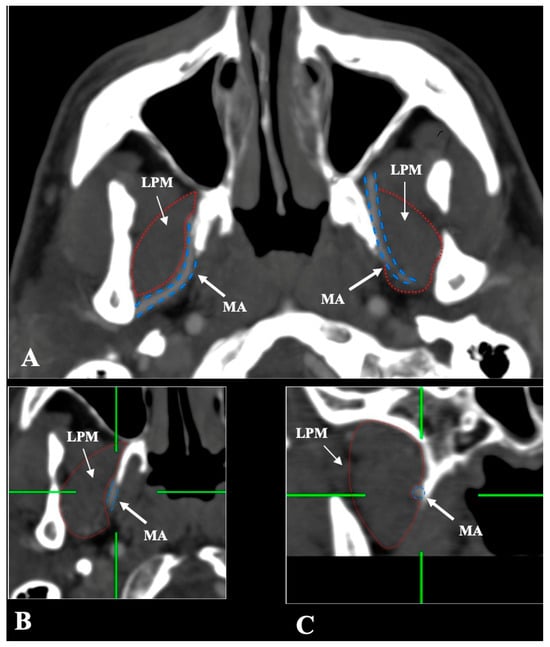

- Intramuscular (transversing the LPM fibers): Found in 31 sides (6.2%), clearly depicted in all planes (Figure 4).